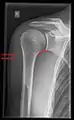

Imaging

Imaging of the shoulder includes ultrasound, X-ray and MRI, and is guided by the suspected diagnosis and presenting symptoms.

Conventional x-rays and ultrasonography are the primary tools used to confirm a diagnosis of injuries sustained to the rotator cuff. For extended clinical questions, imaging through Magnetic Resonance with or without intraarticular contrast agent is indicated.

Hodler et al. recommend starting scanning with conventional x-rays taken from at least two planes, since this method gives a wide first impression and even has the chance of exposing any frequent shoulder pathologies, i.e., decompensated rotator cuff tears, tendinitis calcarea, dislocations, fractures, usures, and/or osteophytes. Furthermore, x-rays are required for the planning of an optimal CT or MR image.[23]

X-ray

Projectional radiography views of the shoulder include:

- AP-projection 40° posterior oblique after Grashey

The body has to be rotated about 30 to 45 degrees towards the shoulder to be imaged, and the standing or sitting patient lets the arm hang. This method reveals the joint gap and the vertical alignment towards the socket.[24]

CR. shoulay film.

Transaxillary conventional radiography

Y-projection conventional radiography